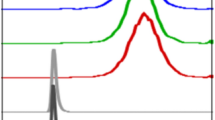

There was a good concordance between predicted doses by 99mTc-MAA-SPECT/CT and actual tumor doses measured on 90Y-PET/CT, with and without RC correction. However, precision (ρ) and accuracy (through the bias coefficient Cb) improved upon dose correction (Fig. 1A–B). Overall, for uncorrected measurements, there was a good agreement with a mean difference of 36.97 Gy between predictive 99mTc-MAA-SPECT/CT dosimetry and 90Y-PET/CT dosimetry, and the majority of points were within the 116.1 Gy standard deviation (SD) (95% LOA: − 190.7–264.6) (Fig. 1C). After RC correction of lesion absorbed doses, agreement improved with a mean difference of − 4.93 Gy between predictive 99mTc-MAA-SPECT/CT dosimetry and 90Y-PET/CT dosimetry, and the majority of points were within the SD (218.3; 95%LOA: − 432.8–422.9) (Fig. 1D).

Comparison of absorbed tumor dose between 90Y-predictive dosimetry by 99mTc-MAA-SPECT/CT and post-SIRT dosimetry on 90Y-PET/CT. Plots illustrating Lin’s concordance correlation coefficient between predicted and effective tumor doses in uncorrected (A) and corrected (B) doses. Dark blue dashed lines represent linear regression fitted with least-squares method and green lines represent perfect concordance. Bland–Altman plot comparing agreement of dose measurements between 90Y-predictive dosimetry by 99mTc-MAA-SPECT/CT and post-SIRT dosimetry without (C) and with dose correction (D).

We obtained a wide range of RC uncorrected and corrected absorbed dose in lesion estimated from the 99mTc-MAA SPECT/CT (range 8–388 and 45–1060 Gy, respectively) and from 90Y-PET/CT (range 15–686 and 46–1586 Gy, respectively) (Table 4). Figure 3 illustrates the effect of the RC correction in estimated lesion absorbed dose from 99mTc-MAA SPECT/CT and 90Y-PET/CT for resin and glass microspheres.

Box plots illustrating the impact of dose correction in absorbed tumor dose between 90Y-predictive dosimetry by 99mTc-MAA-SPECT/CT and post-SIRT dosimetry on 90Y-PET/CT according to the type of microspheres (A). Box plots of predicted-to-actual tumor dose ratios (DR) for resin and glass microspheres (B).